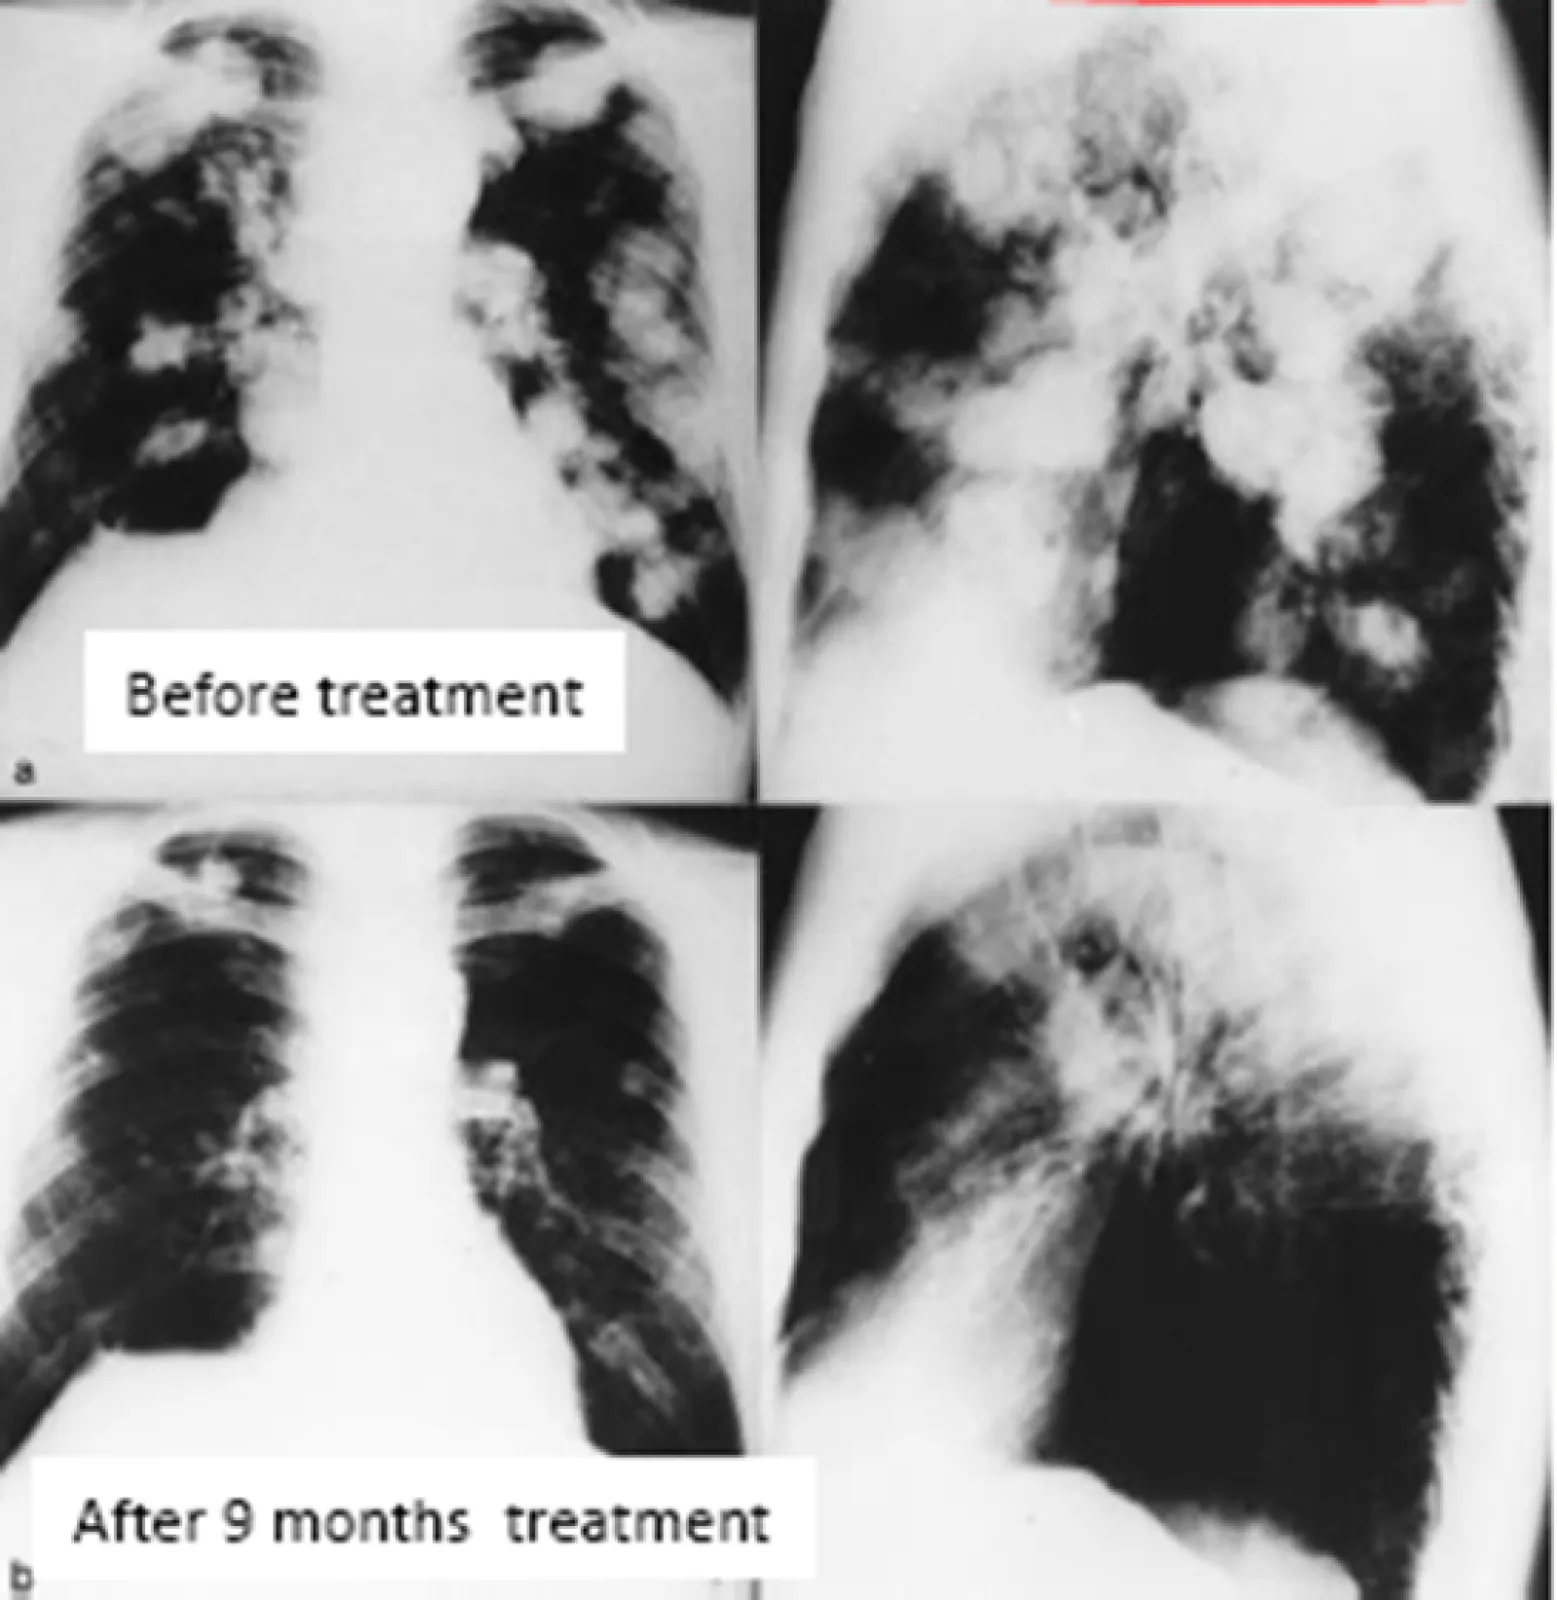

Patient X001 before and after mainly inhalation IL-2 therapy -significant partial response  achieved